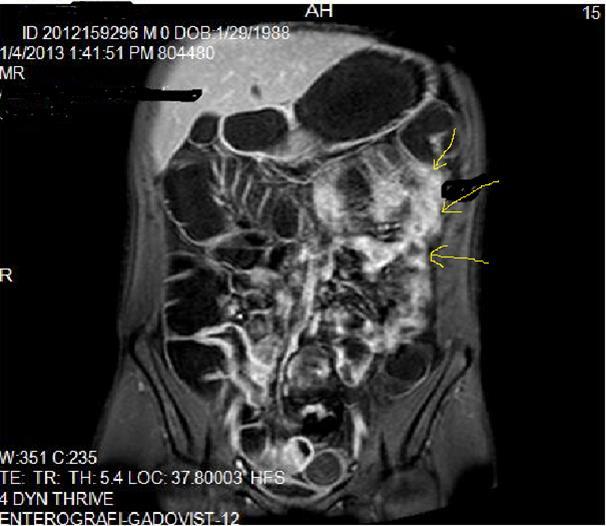

Figure 2a.Concentric luminal narrowing, mural and transmural involvement of terminal ileum due to Crohn’s disease in T2W coronal sequence after OCA application.

Figure 2b.Curvi-lineer, diffuse peripheral enhancing bowel wall in the terminal ileum on axial T1W post-contrast image.